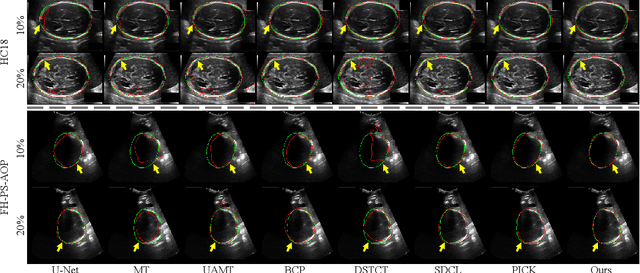

Abstract:Automated segmentation of the fetal head in ultrasound images is critical for prenatal monitoring. However, achieving robust segmentation remains challenging due to the poor quality of ultrasound images and the lack of annotated data. Semi-supervised methods alleviate the lack of annotated data but struggle with the unique characteristics of fetal head ultrasound images, making it challenging to generate reliable pseudo-labels and enforce effective consistency regularization constraints. To address this issue, we propose a novel semi-supervised framework, ERSR, for fetal head ultrasound segmentation. Our framework consists of the dual-scoring adaptive filtering strategy, the ellipse-constrained pseudo-label refinement, and the symmetry-based multiple consistency regularization. The dual-scoring adaptive filtering strategy uses boundary consistency and contour regularity criteria to evaluate and filter teacher outputs. The ellipse-constrained pseudo-label refinement refines these filtered outputs by fitting least-squares ellipses, which strengthens pixels near the center of the fitted ellipse and suppresses noise simultaneously. The symmetry-based multiple consistency regularization enforces multi-level consistency across perturbed images, symmetric regions, and between original predictions and pseudo-labels, enabling the model to capture robust and stable shape representations. Our method achieves state-of-the-art performance on two benchmarks. On the HC18 dataset, it reaches Dice scores of 92.05% and 95.36% with 10% and 20% labeled data, respectively. On the PSFH dataset, the scores are 91.68% and 93.70% under the same settings.